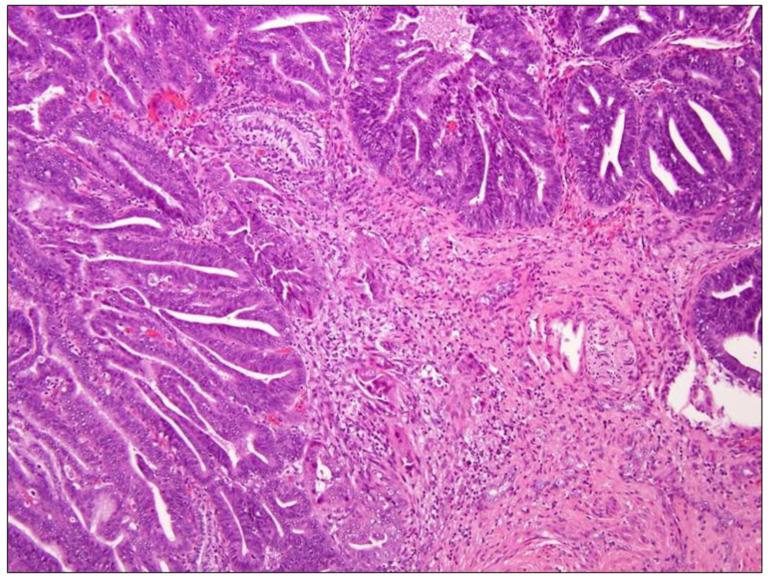

Cervical cancer (CC) is the fourth most frequent cancer in women worldwide. HPV infection is associated with the majority of CC cases, but a small proportion of CCs actually test negative for HPV. The prevalence of HPV among CC histotypes is very different. It has been suggested that HPV-negative CC may represent a biologically distinct subset of tumors, relying on a distinct pathogenetic pathway and carrying a poorer prognosis, than HPV-positive CCs. Although, the discordance in terms of sensitivity and specificity between different HPV tests as well as the potential errors in sampling and storing tissues may be considered as causes of false-negative results. The identification of HPV-negative CCs is essential for their correct management. The aim of this narrative review is to summarize the clinical and pathological features of this variant. We also discuss the pitfalls of different HPV tests possibly leading to classification errors.

宫颈癌(CC)是全球女性中第四常见的癌症。人乳头瘤病毒(HPV)感染与大多数宫颈癌病例相关,但实际上有一小部分宫颈癌HPV检测呈阴性。HPV在宫颈癌组织学类型中的流行率差异很大。有人提出,与HPV阳性宫颈癌相比,HPV阴性宫颈癌可能代表生物学上不同的肿瘤亚群,依赖于不同的致病途径,预后较差。尽管如此,不同HPV检测在敏感性和特异性方面的不一致以及组织采样和储存中的潜在误差可能被视为假阴性结果的原因。识别HPV阴性宫颈癌对于其正确管理至关重要。本叙述性综述的目的是总结该变体的临床和病理特征。我们还讨论了可能导致分类错误的不同HPV检测的陷阱。